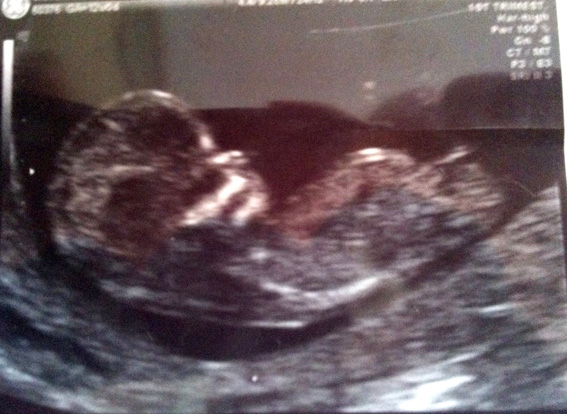

found a clear nub shot from the side.. I think??! Any guesses based on this?! thanks in advance!Attachment 14584

BTW scan taken at 12 weeks!!!

I am going to lean towards boy as the nub itself looks as tho it is on the rise and their is a bump on top :) congrats on a beautiful bubba!

Seems Boyish nub !

Leaning girl 60/40

Slight boy lean :) Update us when you find out!